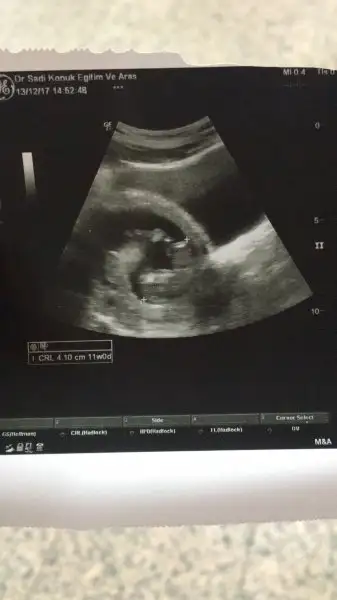

Teşekkür ederim hayırlı sı olsun sağlıkla ... bir rica da daha buluncam bu da 12 haftalık ken

Daha belli değil.. devlet hastanesi ne gidiyor um ben.. ve çok da ilgilenmiyor lar ne yazıkki şu an 12 bitti 13 teyim .. şu ara öğrenirim diye düşünüyorum.. öğrenir öğrenmez yazıcam teşekkür ederim ilgilendiğiniz için.. yinede yorum yapmak isteyenleri bekliyor um

Bu da daha net hali dediğim gbi belli değil henüz doktor a gidemedim